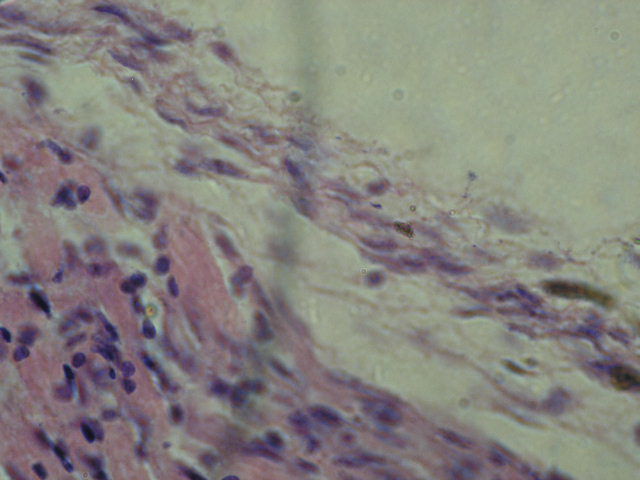

У трахеї інфікованих ПЕ виявлено запальні та деструктивні процеси, в які залучено всі шари слизової оболонки. Так, помірний набряк власно слизової оболонки був зафіксований після інокуляції ПЕ вакцинного штаму 1062 (рис. 4).

Рис.4. Гістологічні зміни трахеї ПЕ, інфікованих вакцинним штамом 1062

а) набряк слизової оболонки трахеї:

б) кровонаповнення судин слизової оболонки трахеї:

в) трахея ПЕ контрольної групи( фарбування гематоксилін-еозин, збільш..Х )

У той же час крім загальних ознак, призводить також до дегенерації епітеліального шару трахеї ПЕ. кровонаповнення судин власно слизової оболонки, відмічено, переродження епітеліальних клітин слизової оболонки трахеї